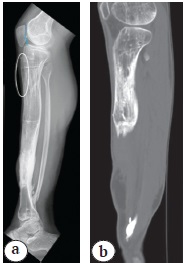

The clinical improvement was immediate with a prompt recovery of knee flexion (ROM 180-90°) and the Caton-Deschamps ratio ranges from 0.51 to 0.83. The external fixator was removed in March 2020 after consolidation was achieved at the docking site and regenerated bone. The Caton-Deschamps ratio comparable to the post-operative one confirmed the correct patellar height (Figure 8). The patient returned to his usual activities of daily living without any sequelae affecting the knee.

Figure 8. AP (a) and lateral X-rays (b) after Ilizarov fixator removal: a — note healing of regenerated bone and docking site; b — restoring of the correct patella height (the Caton-Deschamps ratio of 0.83)